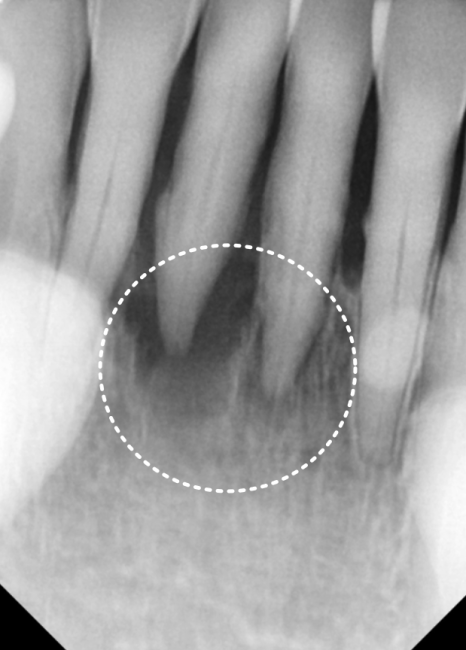

2년 전만 해도 뼈 상태가 양호하고

흔들림도 없으셨던 분인데,

2년 후 다시 뵙게 된 환자분은

아래 앞니 2개가 눈에 띄게 솟구치고

심하게 흔들리는 상태였습니다.

원인은 뿌리 염증으로

잇몸뼈가 녹아

지지력이 사라진 탓이었는데요.

마치 흙이 쓸려 내려간 나무가 들썩이듯,

뼈가 없으니 치아가 위로 밀려 올라온 것이죠.